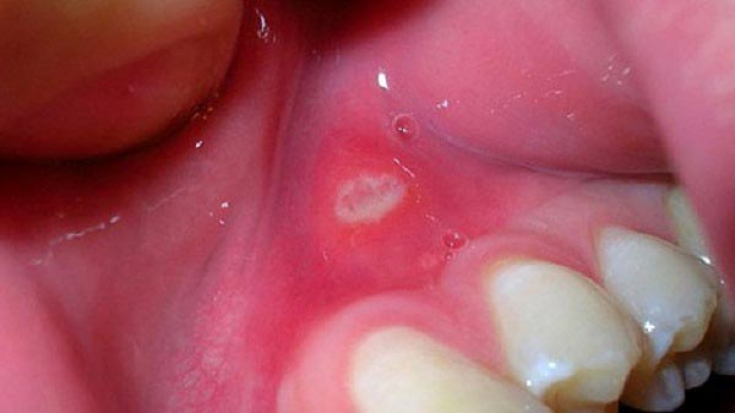

stomatitis more difficult. During illness, the mucous membranes dry out, and when viruses and bacteria enter, they become inflamed. Babies cry all the time, sleep restlessly, it is difficult for them to eat and drink. To diagnose aphthous stomatitis in children, you just need to look into the child's mouth. Any sores, wounds, redness in the oral cavity – an alarm signal and a reason to contact the pediatrician. Aphthae appear simultaneously in several places in the mouth. The focus of inflammation visually looks like a small pimple with a yellow-gray coating with redness around. There is a white coating on the tongue.

Adults have the same symptoms, but aphthae cause less discomfort. There are cases in men and women when the wounds reach a size of 1 centimeter in diameter and leave behind scars.